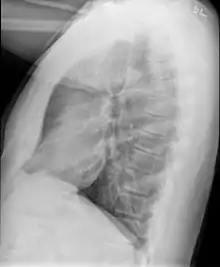

Causes include breathing in toxic fumes, respiratory infections, connective tissue disorder or complications following a bone marrow or heart-lung transplant.[1] Symptoms may not occur until two to eight weeks following toxic exposure or infection.[1] The underlying mechanism involves inflammation that results in scar tissue formation.[1] Diagnosis is by CT scan, pulmonary function tests or lung biopsy.[1] A chest X-ray is often normal.[4]

Bronchiolitis obliterans is often diagnosed based on the symptoms of obstructive lung disease following lung injury. The definitive diagnosis is through biopsy, but due to the variable distribution of lesions, leading to falsely negative tests, and invasive nature of this procedure it is often not performed.[6][11] Several tests are often needed to diagnose bronchiolitis obliterans, including spirometry, diffusing capacity of the lung tests (DLCO), lung volume tests, chest X-rays, high-resolution CT (HRCT), and lung biopsy.[11][4]

Early in the disease chest radiography is typically normal but may show hyperinflation.[6] As the disease progresses a reticular pattern with thickening of airway walls may be present.[4][6] HRCT can also show air trapping when the person being scanned breathes out completely; it can also show thickening in the airway and haziness in the lungs.[11] A common finding on HRCT is patchy areas of decreased lung density, signifying reduced vascular caliber and air trapping.[6] This pattern is often described as a "mosaic pattern", and may indicate bronchiolitis obliterans.[6]